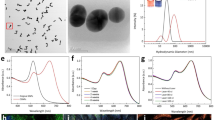

Raw AuNPs were fabricated using femtosecond laser ablation of a gold target submerged in flowing deionized water43. This method uses tightly focused micro-joule (μJ) femtosecond laser pulses to produce nanoparticles, and the size and size distribution of generated nanoparticles can be precisely controlled by optimizing laser parameters, such as wavelength, pulse energy, pulse duration, and repetition rate44. During the pulsed laser ablation, AuNPs were partially oxidized by oxygen present in solution. These Au-O compounds were hydroxylated, followed by a proton loss to give a surface of Au-O−45. Therefore, the Au NPs produced using the laser ablation method are naturally negatively charged and no surfactants and stabilizing ligands are required for maintaining their colloidal stability. Colloidal AuNPs with an average diameter of 20 nm were produced and used in our experiments. Representative TEM image, hydrodynamic particle size distribution and ultraviolet–visible (UV–vis) absorption spectrum are presented in Fig. 1. The generated nanoparticles have a peak size around 20 nm and have an absorption peak at 520 nm due to localized surface plasmon resonance (LSPR). The spectral feature below 450 nm reflects gold intraband transitions since the nanoparticles were generated in deionized water without having other chemical components, such as chemical precursors, reducing agents, and stabilizing ligands, being involved in the fabrication process.

Characterization of synthesized PEGylated gold nanoparticles (PEG-AuNPs): (a) TEM image of 20 nm sized PEG-AuNPs (×2000, 20 kV; bar = 200 nm), (b) particle distribution of PEG-AuNPs estimated by TEM, (c) comparision of hydrodynamic sized bare AuNPs and PEG-AuNPs nanoparticles quantified by dynamic light scattering (DLS) in water, (d) absorption spectra of PEG-AuNPs as function of wavelength at various times (1 day, 7 day, and 1 month), and (e) FT-IR spectra of bare AuNPs, PEG, and PEG-AuNPs, respectively. (f) photostability of PEG-AuNPs after laser irradiation at different energies (40, 80, 160, and 320 nJ) for aperiod of 65 s.

For stabilizing AuNPs under physiological conditions and preventing them from being recognized and eliminated by the human reticuloendothelial system (RES), AuNPs were surface modified with a layer of PEG molecules to improve their stability, biocompatibility, and simultaneously minimize nonspecific interactions with biological tissues by providing a hydrophilic steric barrier. The surface modification of AuNPs with a layer of PEG molecules was performed by adding into them a solution of mPEG-SH5k. The binding of PEG molecules onto the nanoparticles is possible due to strong anchoring of the thiol-gold bonds. Figure 1c compared the hydrodynamic diameters of AuNPs and PEG-AuNPs obtained by DLS measurements. The results showed that the diameter of AuNPs increased over 20 nm after the surface modification with mPEG-SH5k, confirming the result of the binding of thiolated mPEG-SH5k to the surface of AuNPs. The FTIR spectroscopy was also used to confirm the presence of mPEG-SH5k molecules on the surface of AuNPs. As demonstrated in the Fig. 1d, FTIR spectrum of PEG-AuNPs colloidal solution displayed all characteristic peaks that could be found in mPEG-SH5k but not in the AuNPs colloidal solution. In addition, the long term colloidal stability of PEG-AuNPs used in the present study up to a month was evaluated using UV-Vis absorption spectroscopy. As it were shown in the Fig. 1e, there were not any detectable decrease and red shift of LSPR around 520 nm within a month, revealing these PEG-AuNPs remained stable for at least one month. In order to evaluate the photostability of gold nanoparticles during the laser irradiation, we measured UV-vis absorption spectra of the samples after laser exposure at various laser energy (40, 80, 160, and 320 nJ) for a period of 65 s. As shown in Fig. 1(f), colloidal gold nanoparticles show high photostability against laser illumination at the wavelength of 523 nm. It was noticed that the optical spectra show almost no remarkable changes after laser irradiation even at high energy of 320 nJ.